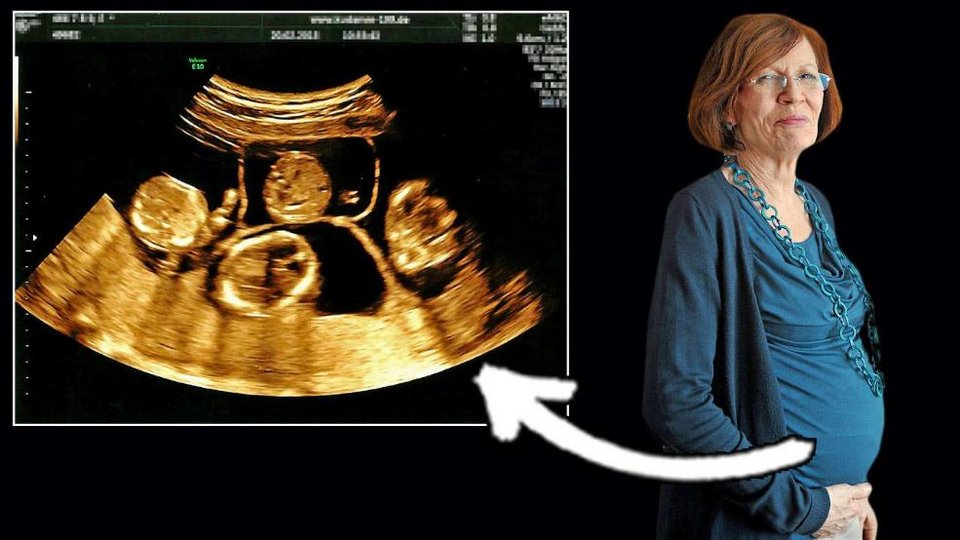

Η 65χρονη γερμανίδα Ανεγκρέτ Ράουνινγκ που είχε προκαλέσει σοκ με την απόφασή της να μείνει ξανά έγκυος στην ηλικία της, γέννηση τετράδυμα και έγινε μητέρα για 17η φορά!

Αυτή η βερολινέζα που πλησιάζει στη σύνταξη είναι η πλέον ηλικιωμένη μητέρα με νεογέννητα στον κόσμο. Τα νεογέννητα γεννήθηκαν πρόωρα, τρία αγόρια και ένα κορίτσι, μετά από μόνο 26 εβδομάδες εγκυμοσύνης και μπήκαν αμέσως σε θερμοκοιτίδα αλλά έχουν πολλές πιθανότητες να επιβιώσουν.

Η γερμανίδα είναι ήδη μητέρα 13 παιδιών και γιαγιά με 7 εγγόνια. Είναι καθηγήτρια αγγλικών και ρωσικών και είχε κάνει πολλές απόπειρες τεχνητής γονιμοποίησης στην Ουκρανία. Η τελευταία της προσπάθεια αποδείχτηκε επιτυχημένη και η εγκυμοσύνη είχε καλό τέλος, αν τα βρέφη επιζήσουν.